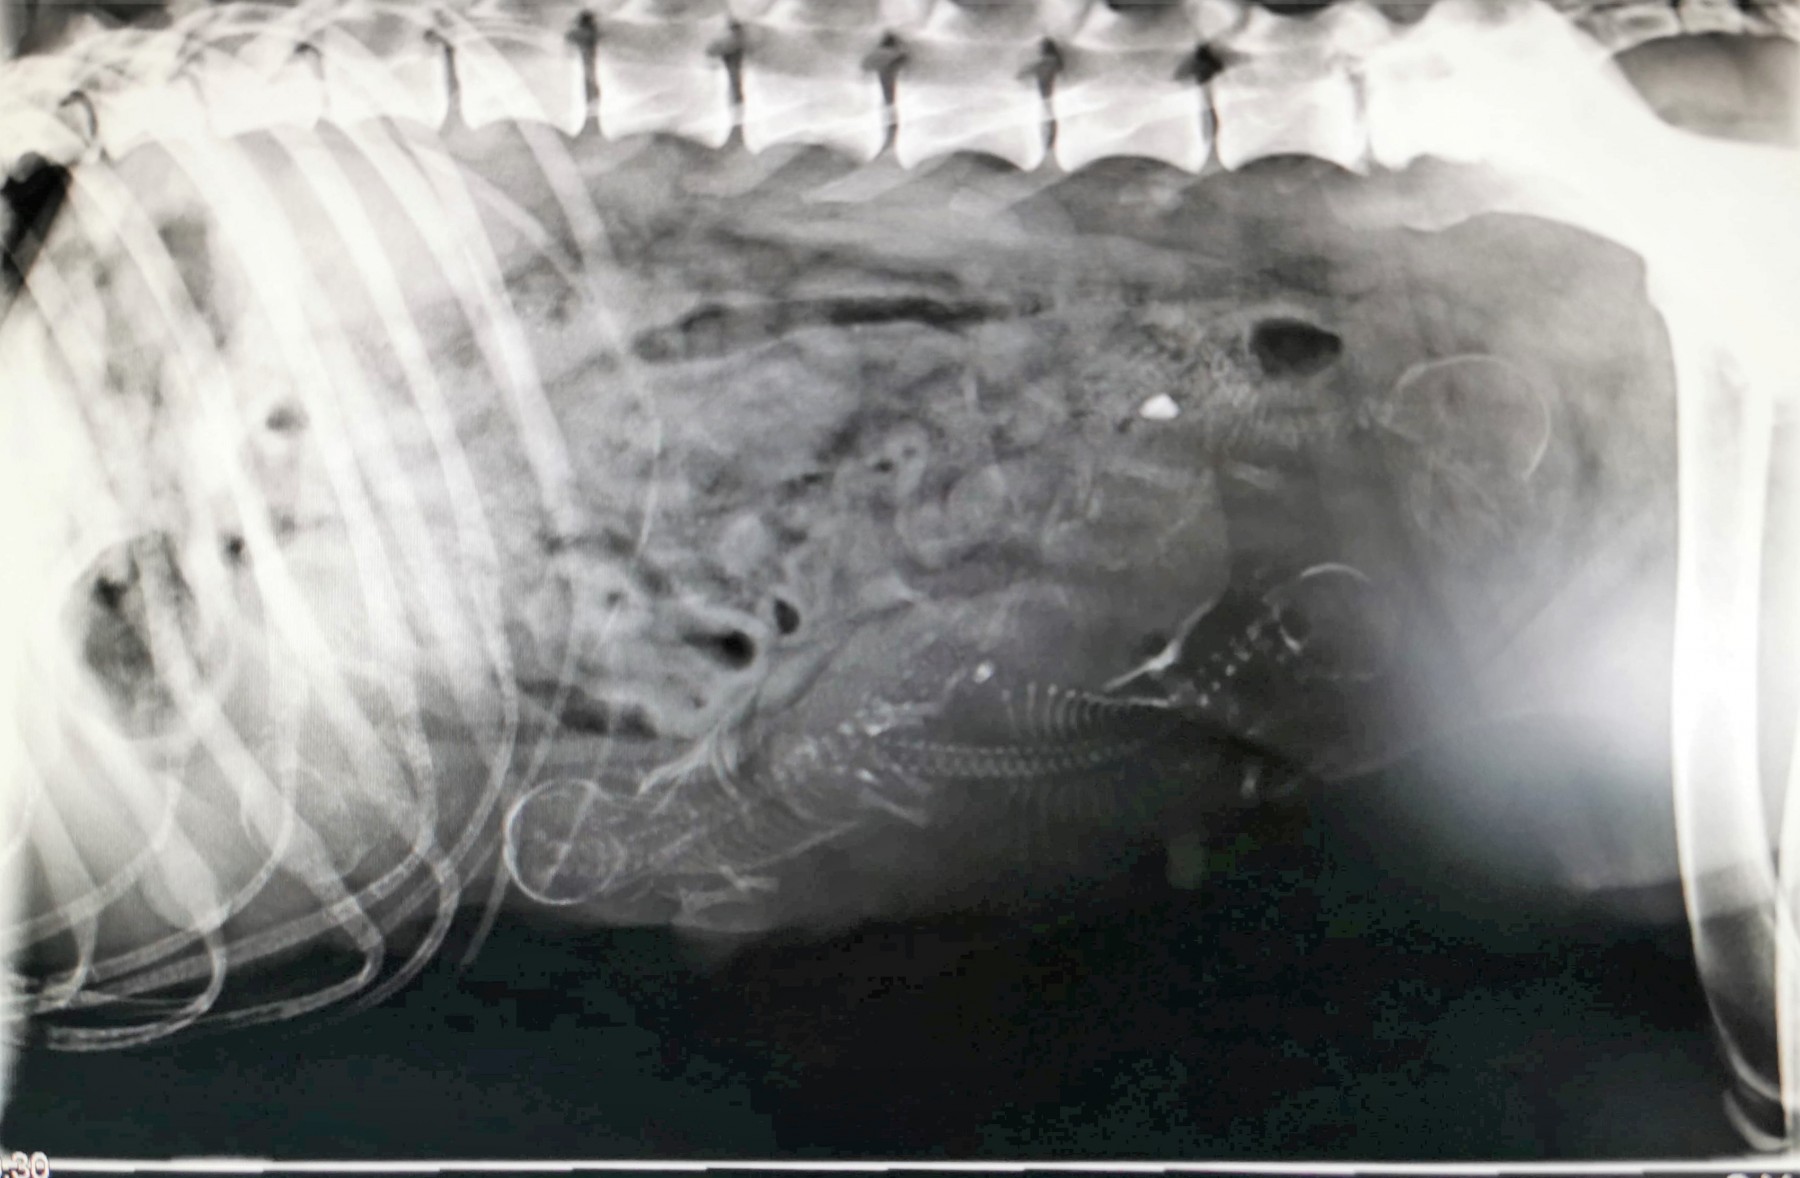

Mange nye bilder fra K-kullet Kull 23.04.2021, 22:03 23.04.2021 Da har det snart gått 2 uker, valpene er 11 dager i dag. De har nå fått sin første ormekur, og vi begynner så vidt å se en liten åpning av øynene. Vi har nå fyllt på med mer bilder i K-kullets fotoalbum. ◄ 1 2 Legg igjen en kommentar: